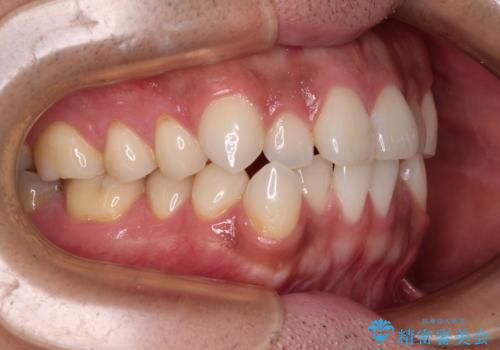

目立たない装置でデコボコを改善 ハーフリンガルによる矯正治療

- 上下顎歯列のデコボコを改善したいとのことで来院された患者様です。

自己管理の大変なインビザラインや、目立つ表側のワイヤー矯正は避けたいとのことで、

上顎だけ裏側装置のハーフリンガルにて矯正しました。

一年と数か月で矯正を終えることができました。

下顎前歯部には後戻り防止のワイヤーを装着しています。